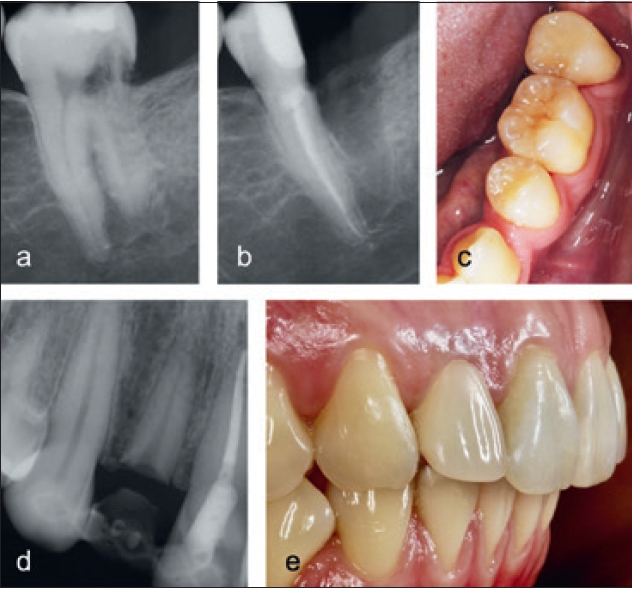

Ersatzresorption (Ankylose)

Dr. Widbiller

Regelmäßige Kontrolle

Falls das Ausmaß der Zerstörung sehr groß und keine Behandlung möglich ist, kann eine temporäre Erhaltung des Zahnes unter engmaschiger Kontrolle in Erwägung gezogen werden [32]. Dazu muss ein entzündungs- und symptomfreier Zustand vorliegen (Abb. 17). Im Zuge regelmäßiger klinischer und radiologischer Kontrollen sollte die Situation gemeinsam mit dem Patienten reevaluiert werden. Ästhetische und funktionelle Beeinträchtigungen wie Zahnverfärbungen, Infrapositionierung oder akute Entzündungen können letzten Endes den Anlass zur Entfernung des geschädigten Zahnes geben.